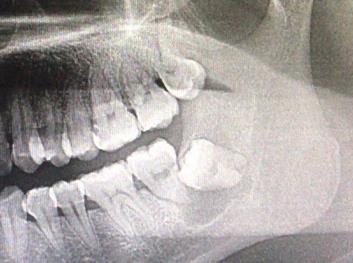

起因:患者于当地诊所拔除右下第二磨牙,拔牙后创口长时间未愈合,经常流出有异味的液体。拍摄口腔全景片示:拔牙窝空虚,右下颌骨发现很大的黑洞。

右下颌骨囊肿